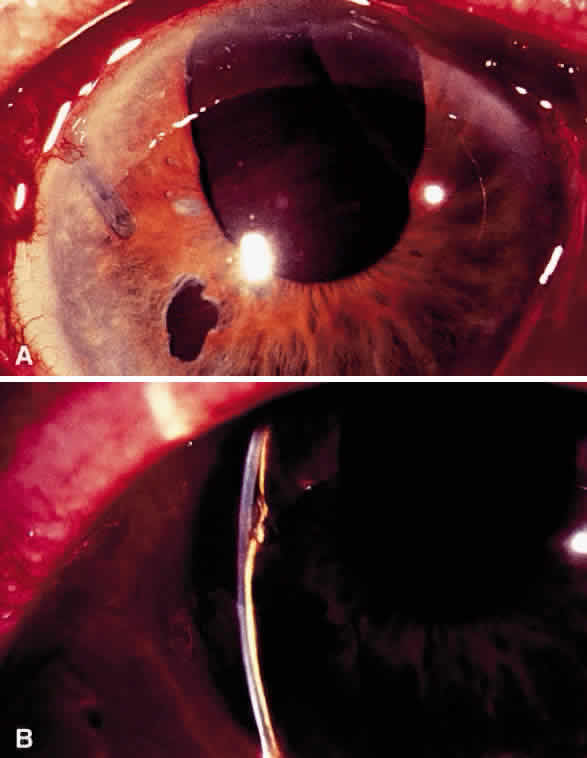

Postoperative suprachoroidal hemorrhage usually occurs within the first week after glaucoma surgery and usually is associated with postoperative hypotony4–6 (Fig. 1). The development of a suprachoroidal hemorrhage typically is acute and associated with the sudden onset of severe pain. Examination of the anterior segment frequently reveals a shallow anterior chamber and a normal or high intraocular pressure (IOP). On fundus examination, a detached and dark choroid is noted. The choroidal elevations have a dark, reddish brown color. Some patients present with bleeding into the vitreous cavity and, uncommonly, retinal detachment. Ultrasonography can be used to diagnose suprachoroidal hemorrhage when fundus examination is not possible.

Intraoperative suprachoroidal hemorrhage can be associated with sudden collapse of the anterior chamber. The patient may complain of sudden pain breaking through the local anesthesia. If the process is gradual, a dark mass can be observed through the pupil to evolve slowly, but if the process is abrupt the hemorrhage is more expulsive.